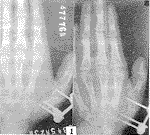

224-t1.gif (4771 bytes)

图1 术后第1天

在掌指骨的侧方或侧背方(尽可能避开肌腱、神经、血管)选择进针点。先在牵引下初步复位后,分别在近、远骨折端的相应皮肤上,用小尖刀纵形切开皮肤2~3 mm,小直血管钳经皮下分离骨膜,用o3.gif (872 bytes) 1.8 mm钻头与骨干纵轴垂直方向钻孔至对侧骨皮质后退出,再用扳手拧入4枚固定针(骨折端远近侧各2枚)。对开放性骨折,在直视下解剖复位后装上支架,拧紧夹块及球形关节固定螺帽将骨折固定稳妥(图1)。对闭合性骨折,用手法整复后同上法装上支架固定,如复位不良,可在透视下重新复位后再作固定。全部病例均行微型支架固定4~8周。